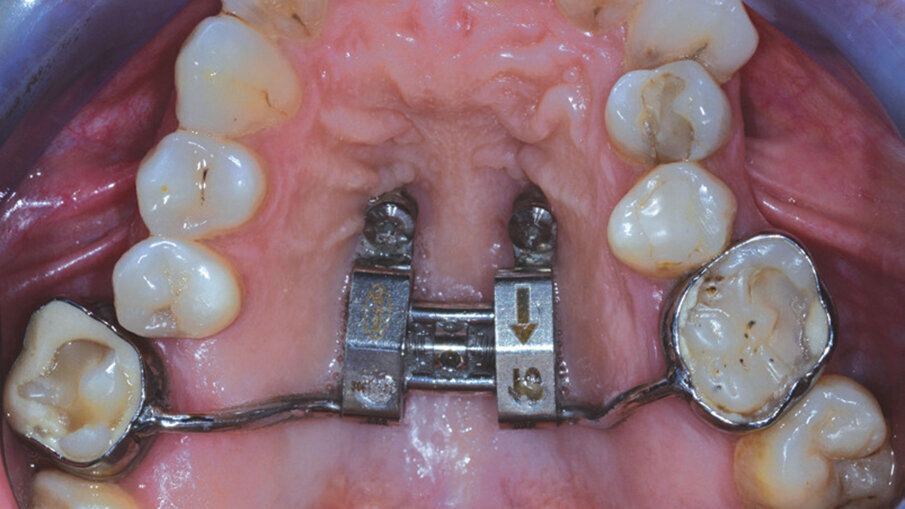

Questo successo ha spinto i produttori a migliorare le caratteristiche dei propri allineatori (materiali, spessore, termoformatura) e introdurre l’utilizzo di dispositivi ausiliari (Figg. 1a-2c) (espansori, bite-ramp, tagli di precisione, elastici), allo scopo di aumentare la predicibilità degli spostamenti dentali ottenibili e la tipologia delle malocclusioni da trattare1-5. Nonostante l’enorme mobilitazione di risorse finanziarie in tutto il mondo, finalizzate alla produzione di nuove linee di prodotti, sono pochi gli studi clinici e le prove di alta qualità sulla reale efficacia di tale trattamento, per stabilire l’affidabilità concreta degli allineatori dentali nella terapia ortodontica; sappiamo sicuramente che la durata di trattamento e il tempo alla poltrona ridotti sembrano essere vantaggi sostanziali degli allineatori rispetto ai sistemi convenzionali, oltre ad assicurare una migliore estetica, un grande comfort, un più facile mantenimento dell’igiene orale e una migliore salute parodontale. Tuttavia, sulla base dell’attuale evidenza scientifica disponibile, la terapia con allineatori dentali è efficace soprattutto nella gestione di malocclusioni lievi e mostra risultati accettabili per il trattamento di malocclusioni moderate6.

Figg. 1a, 1b_Utilizzo di dispositivi ausiliari (REP su miniviti nella foto a sinistra e bottoni linguali con trazione elastica nella foto di destra) per aumentare la predicibilità dei trattamenti con allineatori dentali ALLEO.

Figg. 1a, 1b_Utilizzo di dispositivi ausiliari (REP su miniviti nella foto a sinistra e bottoni linguali con trazione elastica nella foto di destra) per aumentare la predicibilità dei trattamenti con allineatori dentali ALLEO.

Figg. 2a-2c_Utilizzo del dispositivo ALLEO+ come ausiliare per espandere e ottenere spazio in arcata superiore, al fine di utilizzare, successivamente, un numero di allineatori ridotto e una minore quantità di stripping.

Figg. 2a-2c_Utilizzo del dispositivo ALLEO+ come ausiliare per espandere e ottenere spazio in arcata superiore, al fine di utilizzare, successivamente, un numero di allineatori ridotto e una minore quantità di stripping.

Figg. 2a-2c_Utilizzo del dispositivo ALLEO+ come ausiliare per espandere e ottenere spazio in arcata superiore, al fine di utilizzare, successivamente, un numero di allineatori ridotto e una minore quantità di stripping.